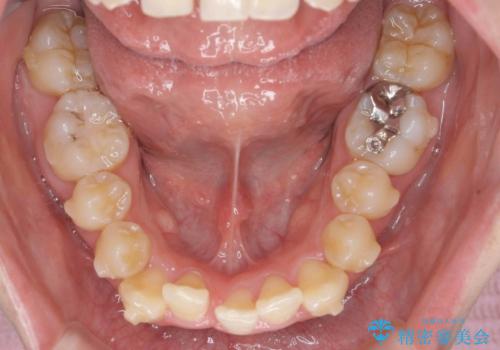

前歯のがたつきをマウスピース矯正できれいに!

- 目立つ前歯のがたつきを改善したい、と矯正治療を希望され来院されました。

今回の治療ではシミュレーションでしっかりと検討した結果、下顎は前歯を1本抜去し仕上げる治療計画としました。